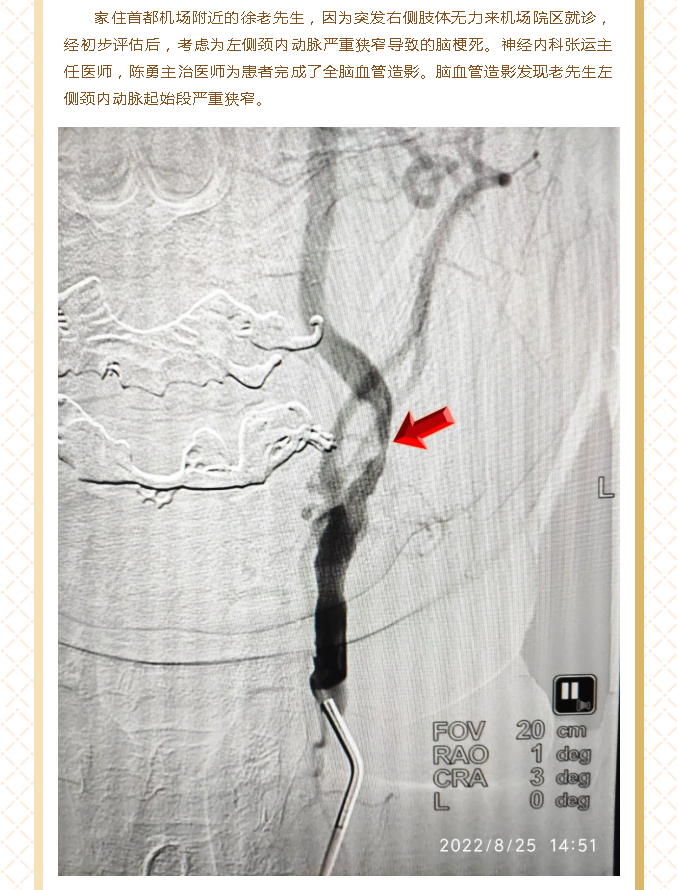

北医三院机场院区导管室顺利开展首例脑血管造影及颈动脉狭窄支架植入术